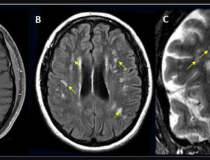

This photo gallery shows the variety of radiological presentations of COVID-19 (SARS-CoV-2) in medical imaging, including computed tomography (CT), radiograph X-rays, ultrasound, echocardiograms and magnetic resonance imaging (MRI). The radiology images show examples of typical COVID pneumonia in the lungs and the numerous complications the virus causes in the body in multiple organs, including the brain, kidneys, heart, abdomen and vascular system.

Ultrasound, especially hand-held ultrasound imaging devices, have become a primary imaging modality for novel coronavirus because of the ease to bag the device and sterilize it after use. CT and mobile X-ray systems are also used as front-line imaging systems for COVID-positive or suspected COVID patients.